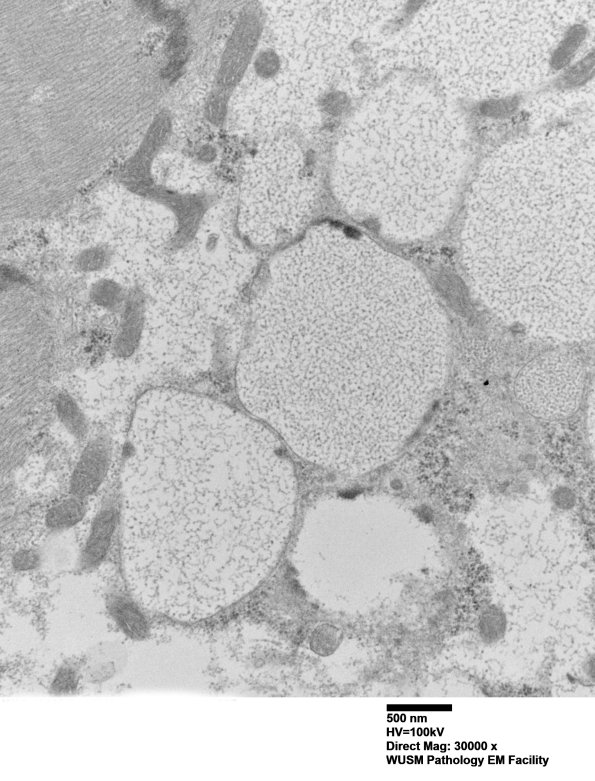

Washington University Experience | METABOLIC | Pompe Disease | 5D14 Muscle (Case 5) EM027 - Copy

There are multiple membrane bound elements under the sarcolemma. (electron micrographs) ---- Additional results: Biochemical studies of the muscle showed a marked increase in glycogen (394 μg/mg protein vs. normal 0.015).